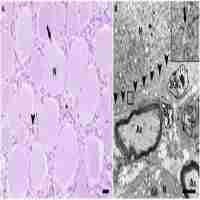

| Abstract | The volumes of the nerve cell bodies and those of the enveloping satellite cell sheaths from spinal ganglia were determined by morphometric methods applied to electron micrographs in young, adult, old and very old rabbits. The mean volume of the nerve cell bodies increased progressively with age; this is probably related to the increase with age of the body size of the rabbits studied. The mean volume of the satellite cell sheaths did not differ significantly in young, adult and old animals, but was significantly smaller in very old animals. It is extremely unlikely that this marked reduction in the volume of the satellite cell sheath is the result of a pathological process. The mean value of the volume ratio between the satellite cell sheaths and the related nerve cell bodies did not differ significantly in young and adult animals, but was significantly smaller in old and very old animals. This ratio was particularly low in very old animals. Our analysis showed that in each age group the volume of the satellite cell sheath is linearly related to the volume of the related nerve cell body. This result suggests that in rabbit spinal ganglia the quantitative relations between glial and nervous tissue are tightly controlled throughout life. It is suggested that ganglionic neurons release signals to influence and control the volume of their associated glial tissue. Since satellite cells have important support roles for the neurons they surround, it is likely that the marked reduction in the volume of perineuronal sheaths in the extremely advanced age is accompanied by a reduction of those roles, with negative consequences for neuronal activity. |